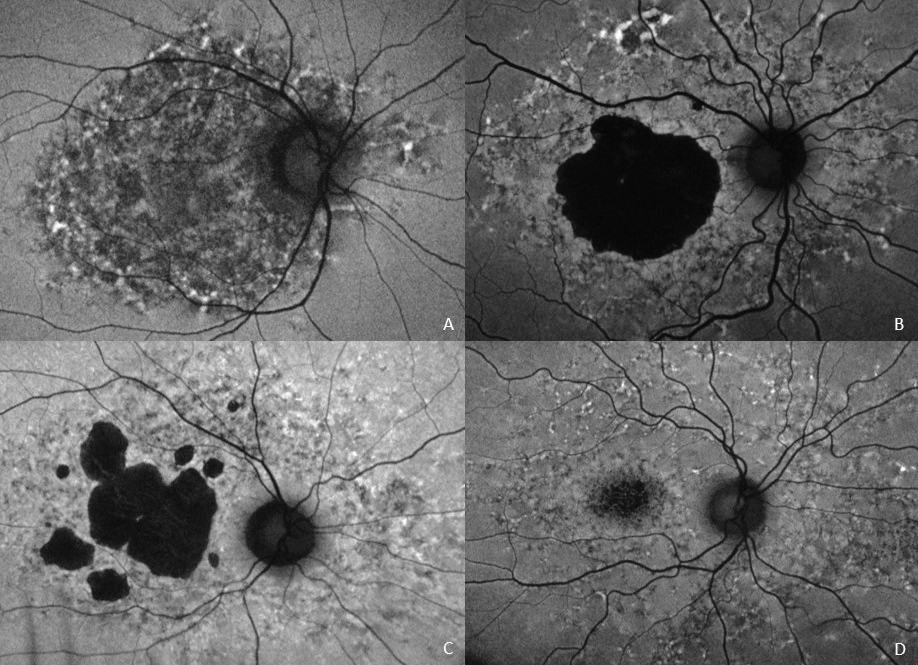

Most cases of pentosan polysulfate maculopathy that involve the peripapillary retina, demonstrate a hypoautofluorescent peripapillary ring (A). The autofluorescent signal is spared in many inherited macular dystrophies such as this dominant macular dystrophy associated with a variant of unknown significance in the ELOVL4 gene (B), another macular dystrophy associated with a disease-causing PRPH2 variant (C), and two disease-causing ABCA4 variants (D). Reprinted with permission from Elsevier from: Barnes AC, Hanif AM, Jain N. Pentosan polysulfate maculopathy versus inherited macular dystrophies: comparative assessment with multimodal imaging. Ophthalmol Retina. Published online May 21, 2020. doi:10.1016/j.oret.2020.05.008